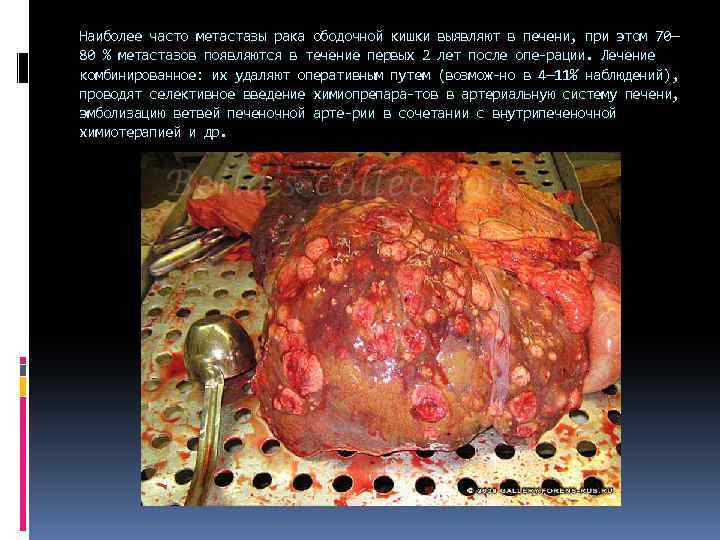

Наиболее часто метастазы рака ободочной кишки выявляют в печени, при этом 70— 80 % метастазов появляются в течение первых 2 лет после опе рации. Лечение комбинированное: их удаляют оперативным путем (возмож но в 4— 11% наблюдений), проводят селективное введение химиопрепара тов в артериальную систему печени, эмболизацию ветвей печеночной арте рии в сочетании с внутрипеченочной химиотерапией и др.